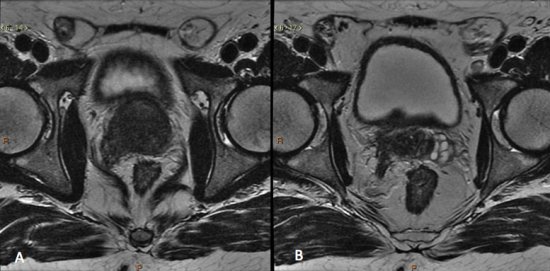

No estadiamento locorregional do câncer de próstata, o aspecto mais relevante na tomada de decisão terapêutica é a diferenciação entre tumor confinado ao órgão (T1 e T2) e tumor localmente avançado, sob as formas de extensão extraprostática (T3a) ou invasão de vesículas seminais (T3b). Para esta avaliação, as imagens ponderadas em T2 são as mais indicadas15,18

Os achados que indicam invasão das vesículas seminais incluem: aumento de tamanho, assimetria e hipointensidade das vesículas seminais, obliteração do ângulo vesicoprostático e extensão direta da base prostática à vesícula seminal, sendo este achado o de maior valor preditivo positivo.15,18 (fig. 5 e 6).

Figura 6. Estadiamento de adenocarcinoma da próstata Gleason 9. A) Lesão hipointensa comprometendo quase toda a glândula, com extensão para a gordura periprostática à direita. B) Comprometimento das vesículas seminais.